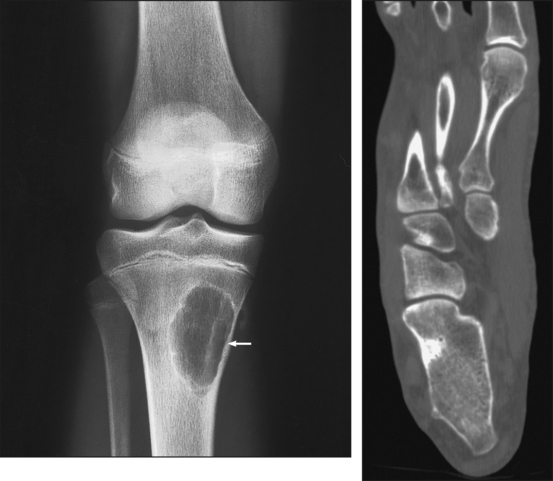

The tibia (Fig. 6-4) is the larger of the two bones of the leg and consists of one body and two expanded extremities. The proximal end of the tibia has two prominent processes—the medial and lateral condyles. The superior surfaces of the condyles form smooth facets for articulation with the condyles of the femur. These two flatlike superior surfaces are called the tibial plateaus, and they slope posteriorly about 10 to 20 degrees. Between the two articular surfaces is a sharp projection, the intercondylar eminence, which terminates in two peaklike processes called the medial and lateral intercondylar tubercles. The lateral condyle has a facet at its distal posterior surface for articulation with the head of the fibula. On the anterior surface of the tibia, just below the condyles, is a prominent process called the tibial tuberosity, to which the ligamentum patellae attach. Extending along the anterior surface of the tibial body, beginning at the tuberosity, is a sharp ridge called the anterior crest.

Fig. 6-4 Right tibia and fibula. A, Anterior aspect. B, Posterior aspect. C, Lateral aspect. D, Proximal end of tibia and fibula showing angle of tibial plateau. E, Photograph of superior and posterior aspect of the tibia.

The distal end of the tibia (Fig. 6-5) is broad, and its medial surface is prolonged into a large process called the medial malleolus. Its anterolateral surface contains the anterior tubercle, which overlays the fibula. The lateral surface is flattened and contains the triangular fibular notch for articulation with the fibula. The surface under the distal tibia is smooth and shaped for articulation with the talus.